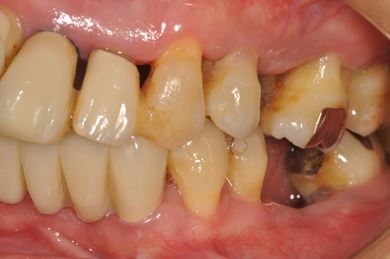

インプラントの症例写真 IMPLANT

骨再生スピードインプラント治療+セラミック治療

| 性別/年齢 | 女性 / 43歳 | ||||||||||||||||||||||||||||||||

| 主訴 | 骨が薄いが、インプラント治療を希望。 | ||||||||||||||||||||||||||||||||

| 治療内容 | インプラント9本(抜歯即日スピードインプラント、ソケットリフト、テンポラリーインプラント+仮歯)、メタルボンドセラミッククラウン18本、メタルボンドセラミックブリッジ6本(メタルボンド用土台6本)、遊離歯肉移植術 | ||||||||||||||||||||||||||||||||